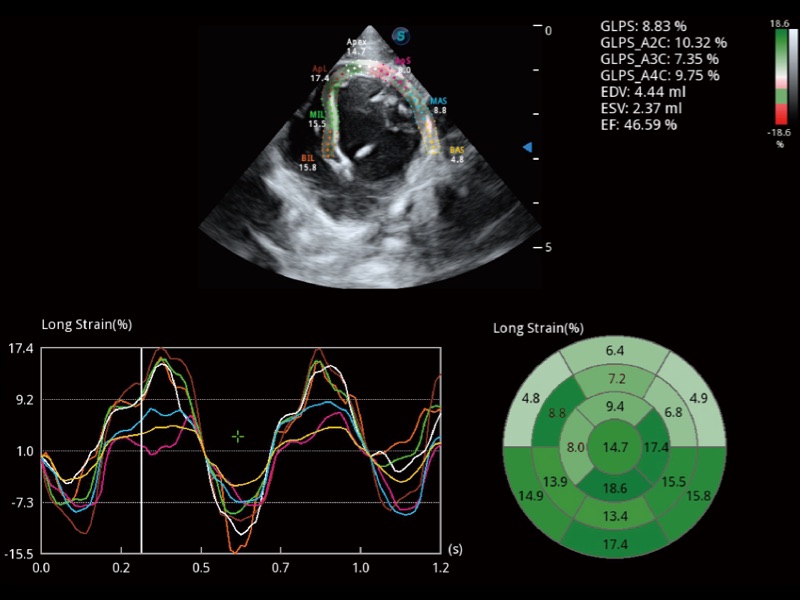

• Auto EF 心内膜自动描迹

能够基于左心室壁追踪和辛普森法,自动计算射血分数,支持多个可移动点描迹,与手动测量相比,极大节省了动物医生的时间和精力。

(犬)四腔心

(犬)四腔心MQA